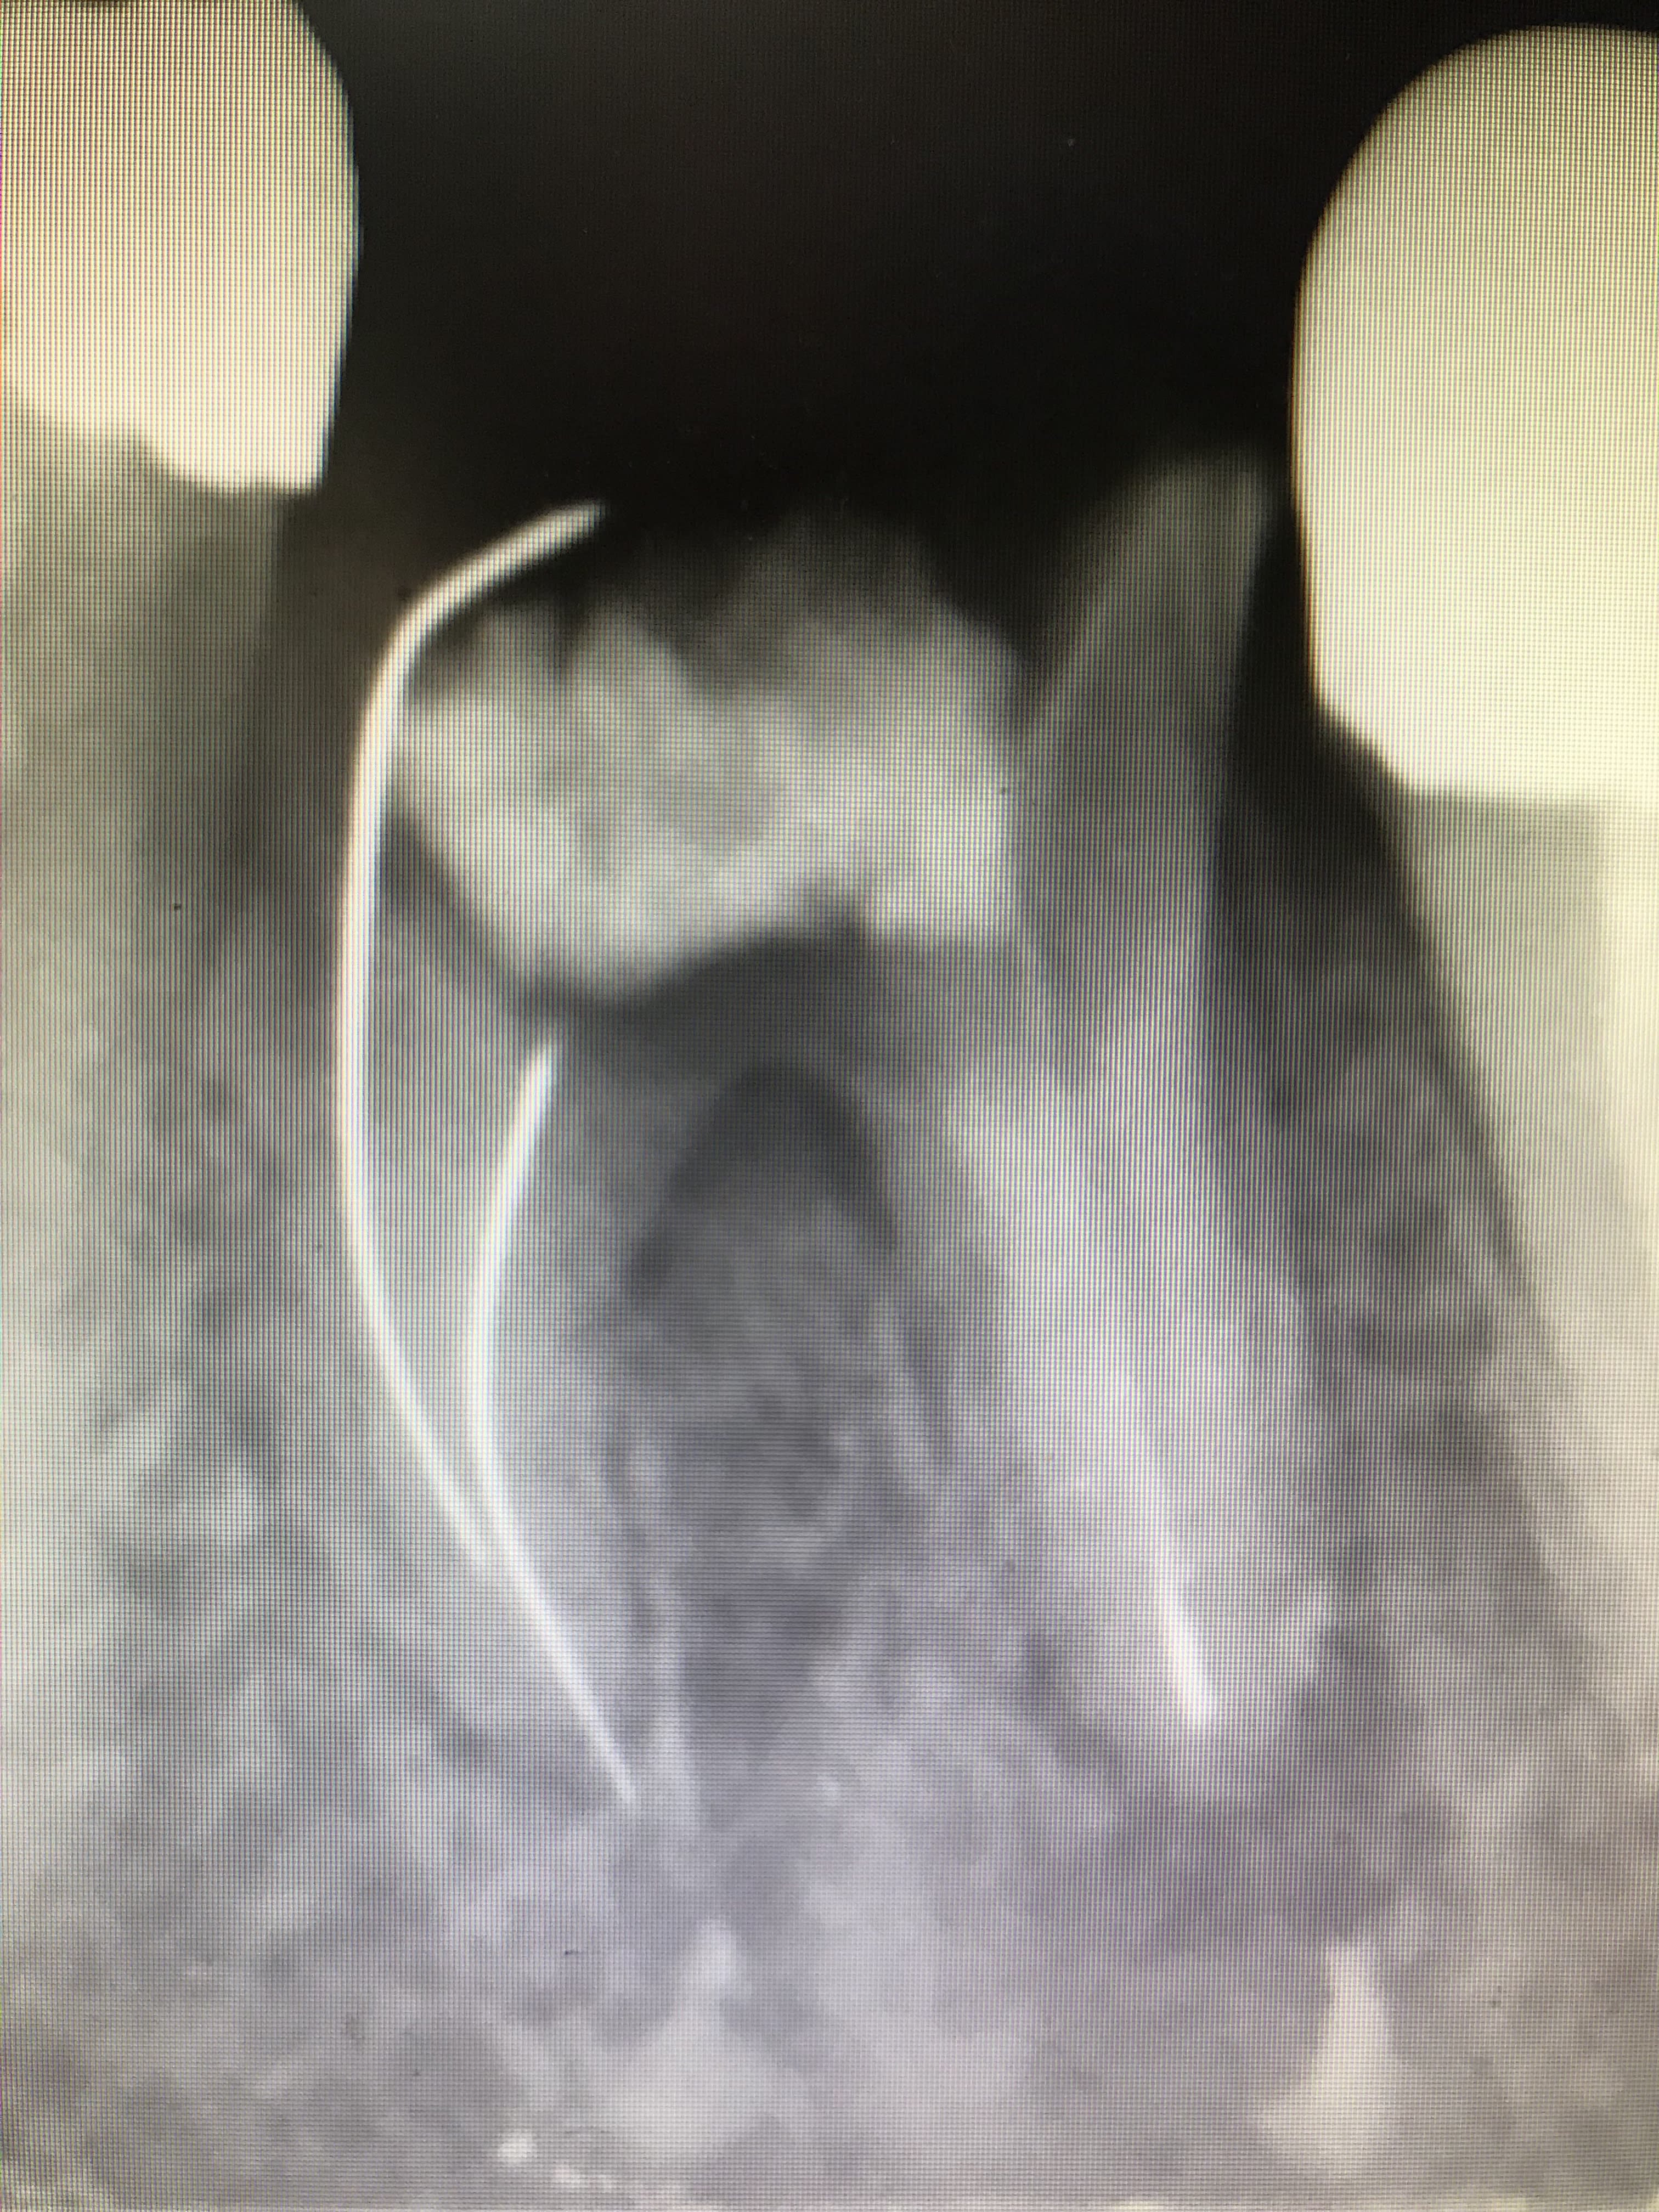

Tiens une petite obturation comme vous saviez si bien le faire par le passé (vu récemment au cabinet) :) :

1f6b377d fba5 4214 aa5b bd4692f8eefd yutxjk - Eugenol